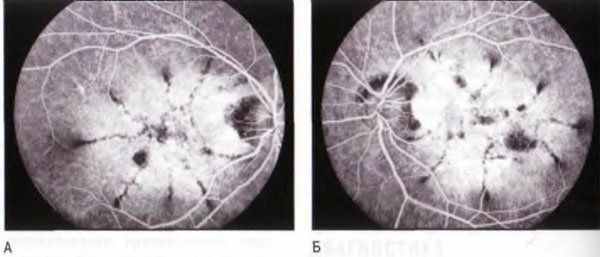

Рис. 6-8. Паттерн-дистрофия, порошкообразное глазное дно.

А, Б. На ангиографических снимках обоих глаз отмечается лучеобразно расходящийся рисунок гипофлюоресценции вследствие образования грубых пигментных отложений, на уровне пигментного эпителия. (Публикуется с разрешения Dr. William Annestey, and the Retina Slide Collection. Wills Eye Hospital, Philadelphia. Pennsylvania, compiled by Dr. Tamara Vrabec and Dr. Gordon Byrnes.)